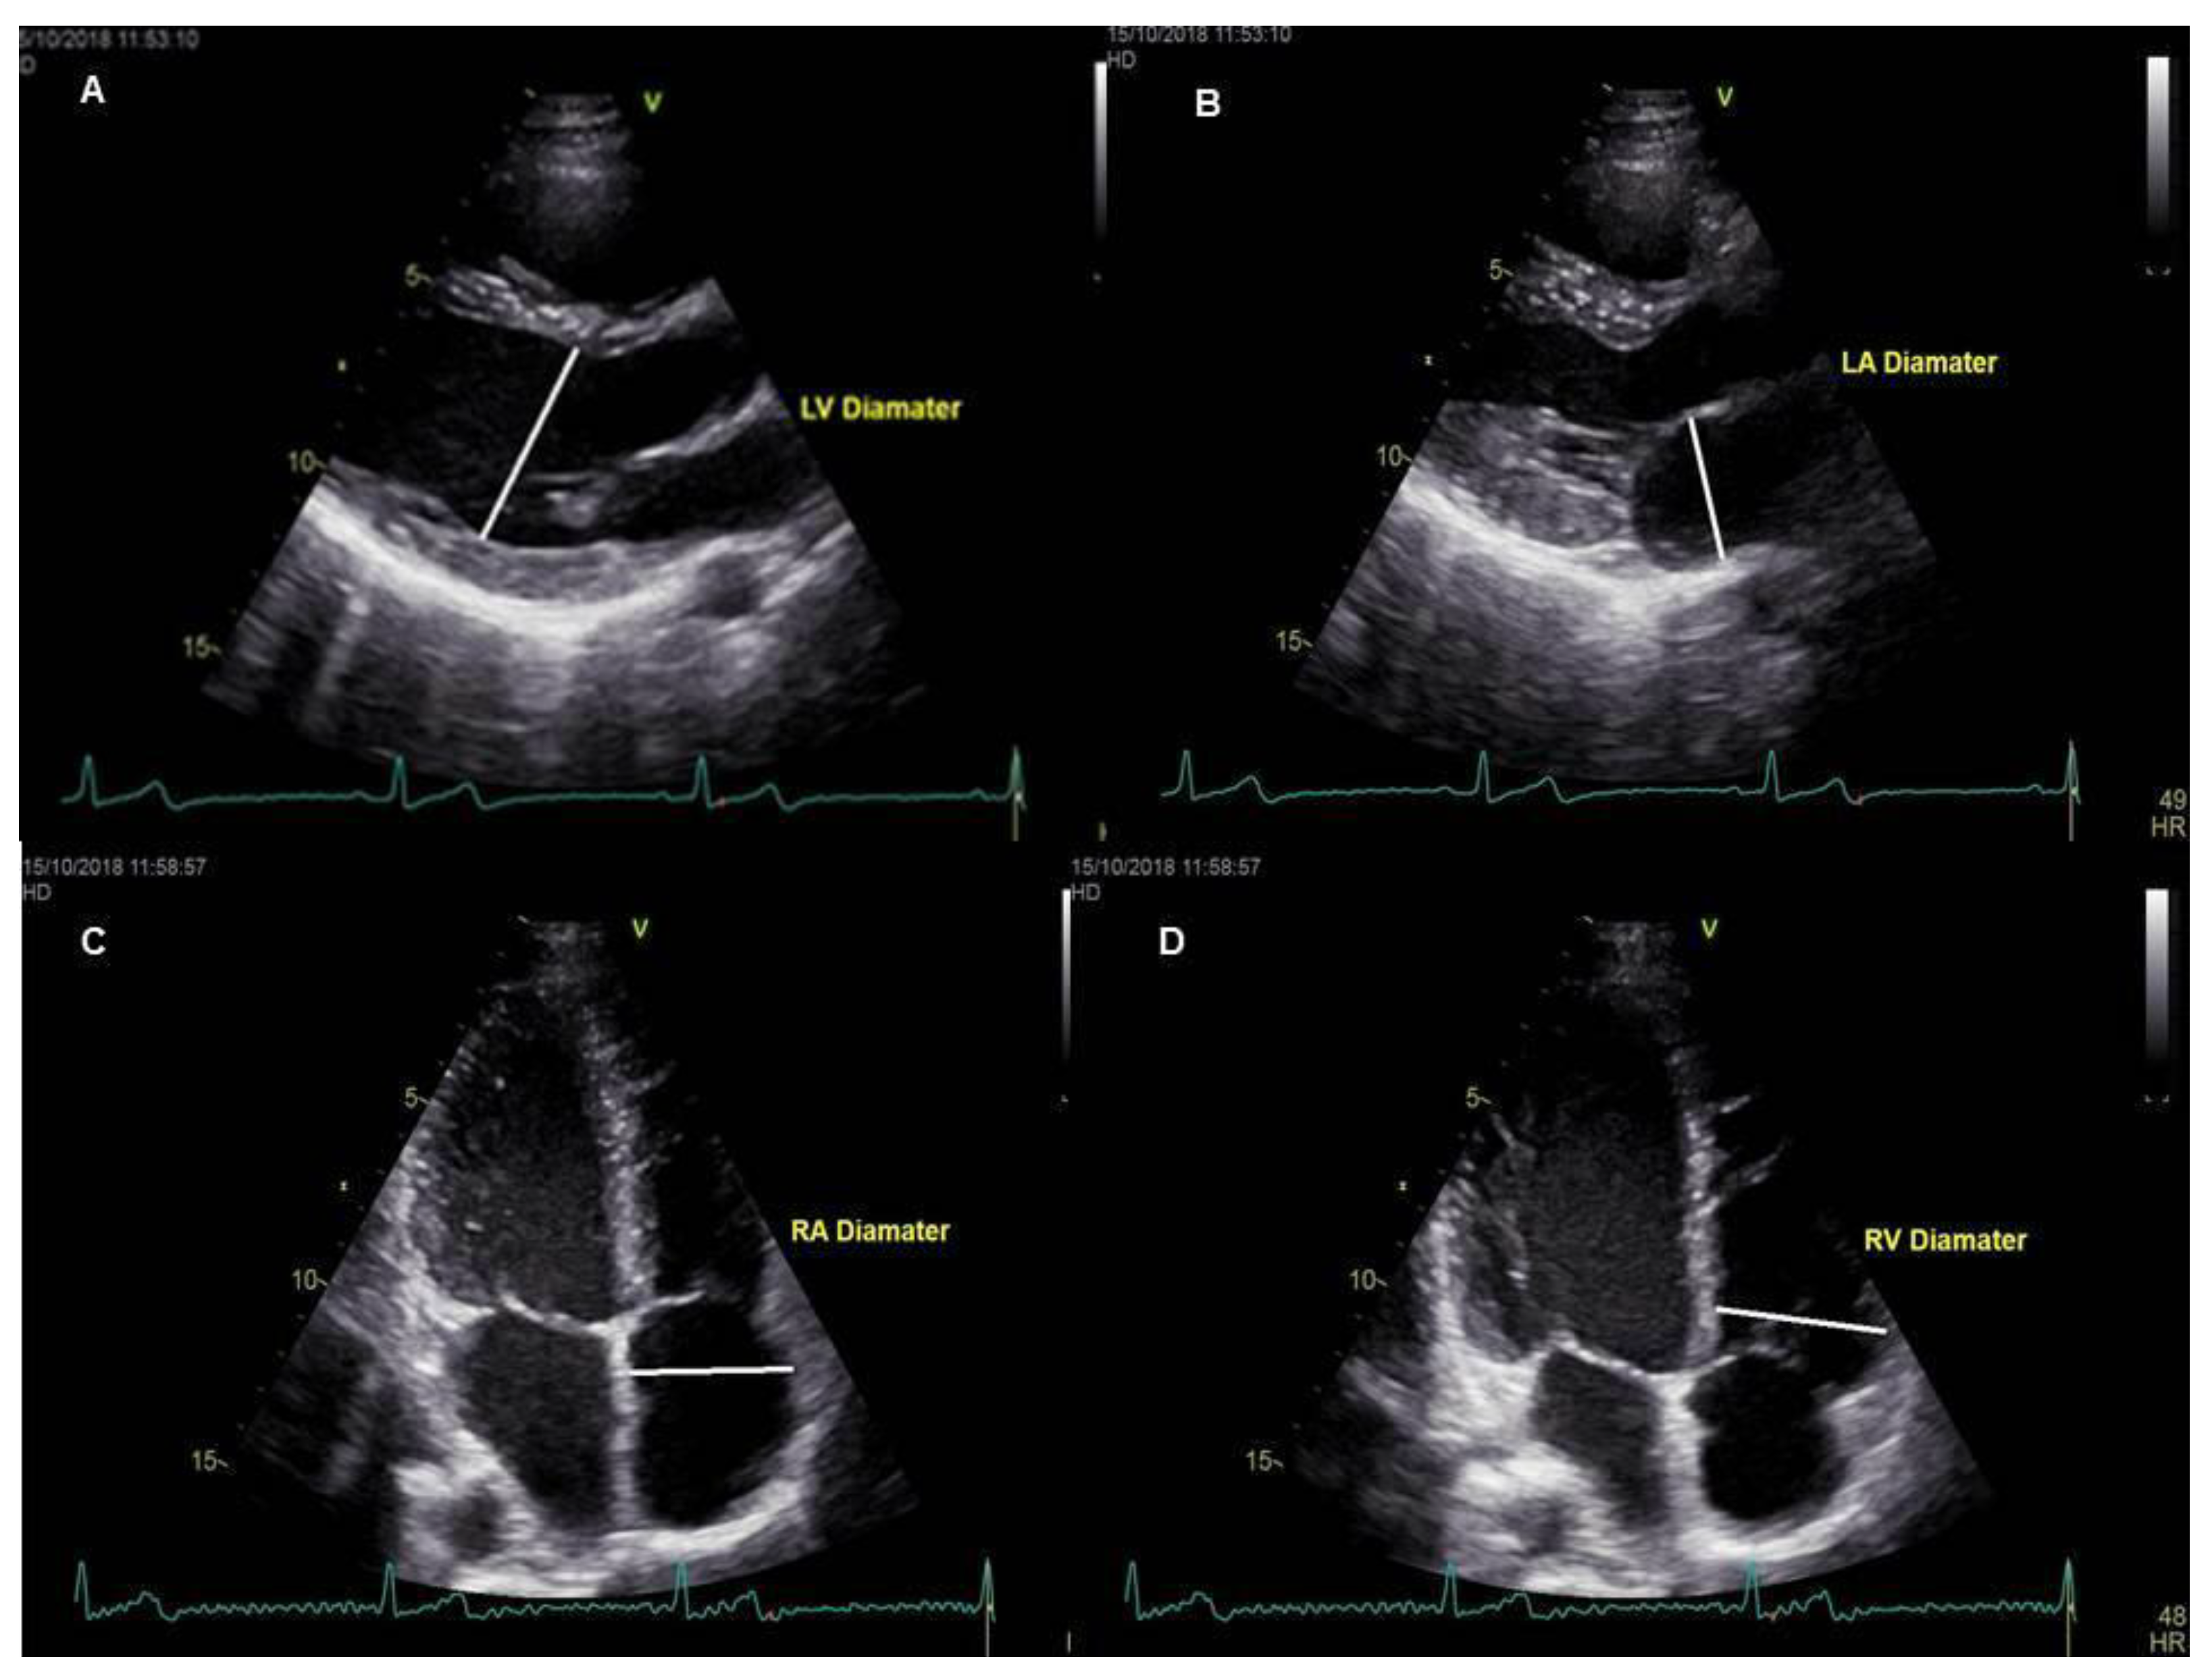

2. Materials and Methods

2.1. Subject Selection and Imaging Protocols